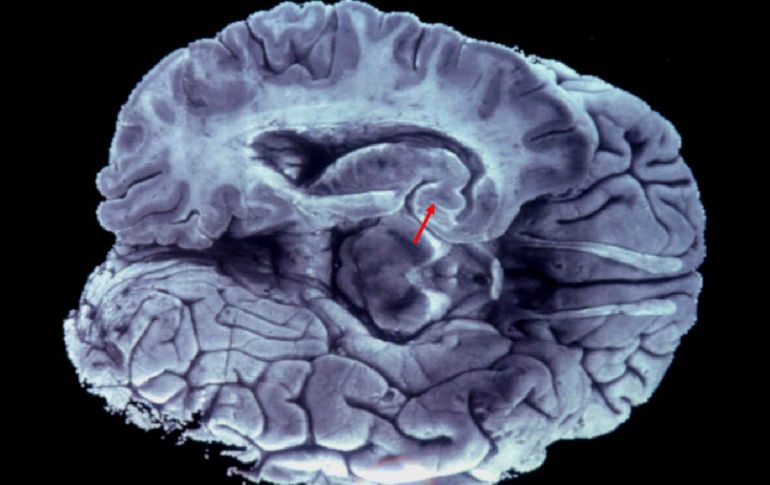

La fotografía muestra las lesiones histopatológicas características de la enfermedad de Alzheimer en el cerebro. EFE  ARCHIVO  /